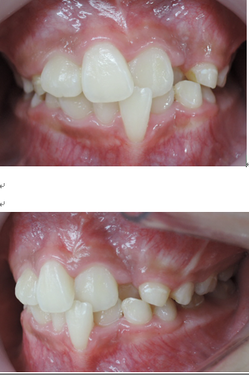

今回の症例は、悪い歯並びの代表例である八重歯です。

歯並びが悪いだけでなく、困ったことに犬歯から奥歯にかけて歯が嚙み合っていない開咬の状態です。

一般的な矯正の治療法では中心から4番目の歯を抜いて隙間をつくり、飛び出した犬歯を並べて治療します。

しかし、この矯正方法は歯を横に動かす治療法なので、噛んだときにできる奥歯の上下の隙間を治すのが苦手です。

当院ではマルチループ(MEAW法)という上の写真で装着しているようなクネクネ曲がったワイヤーを使用して、上下の隙間を埋めていくことで歯並びを整えます。